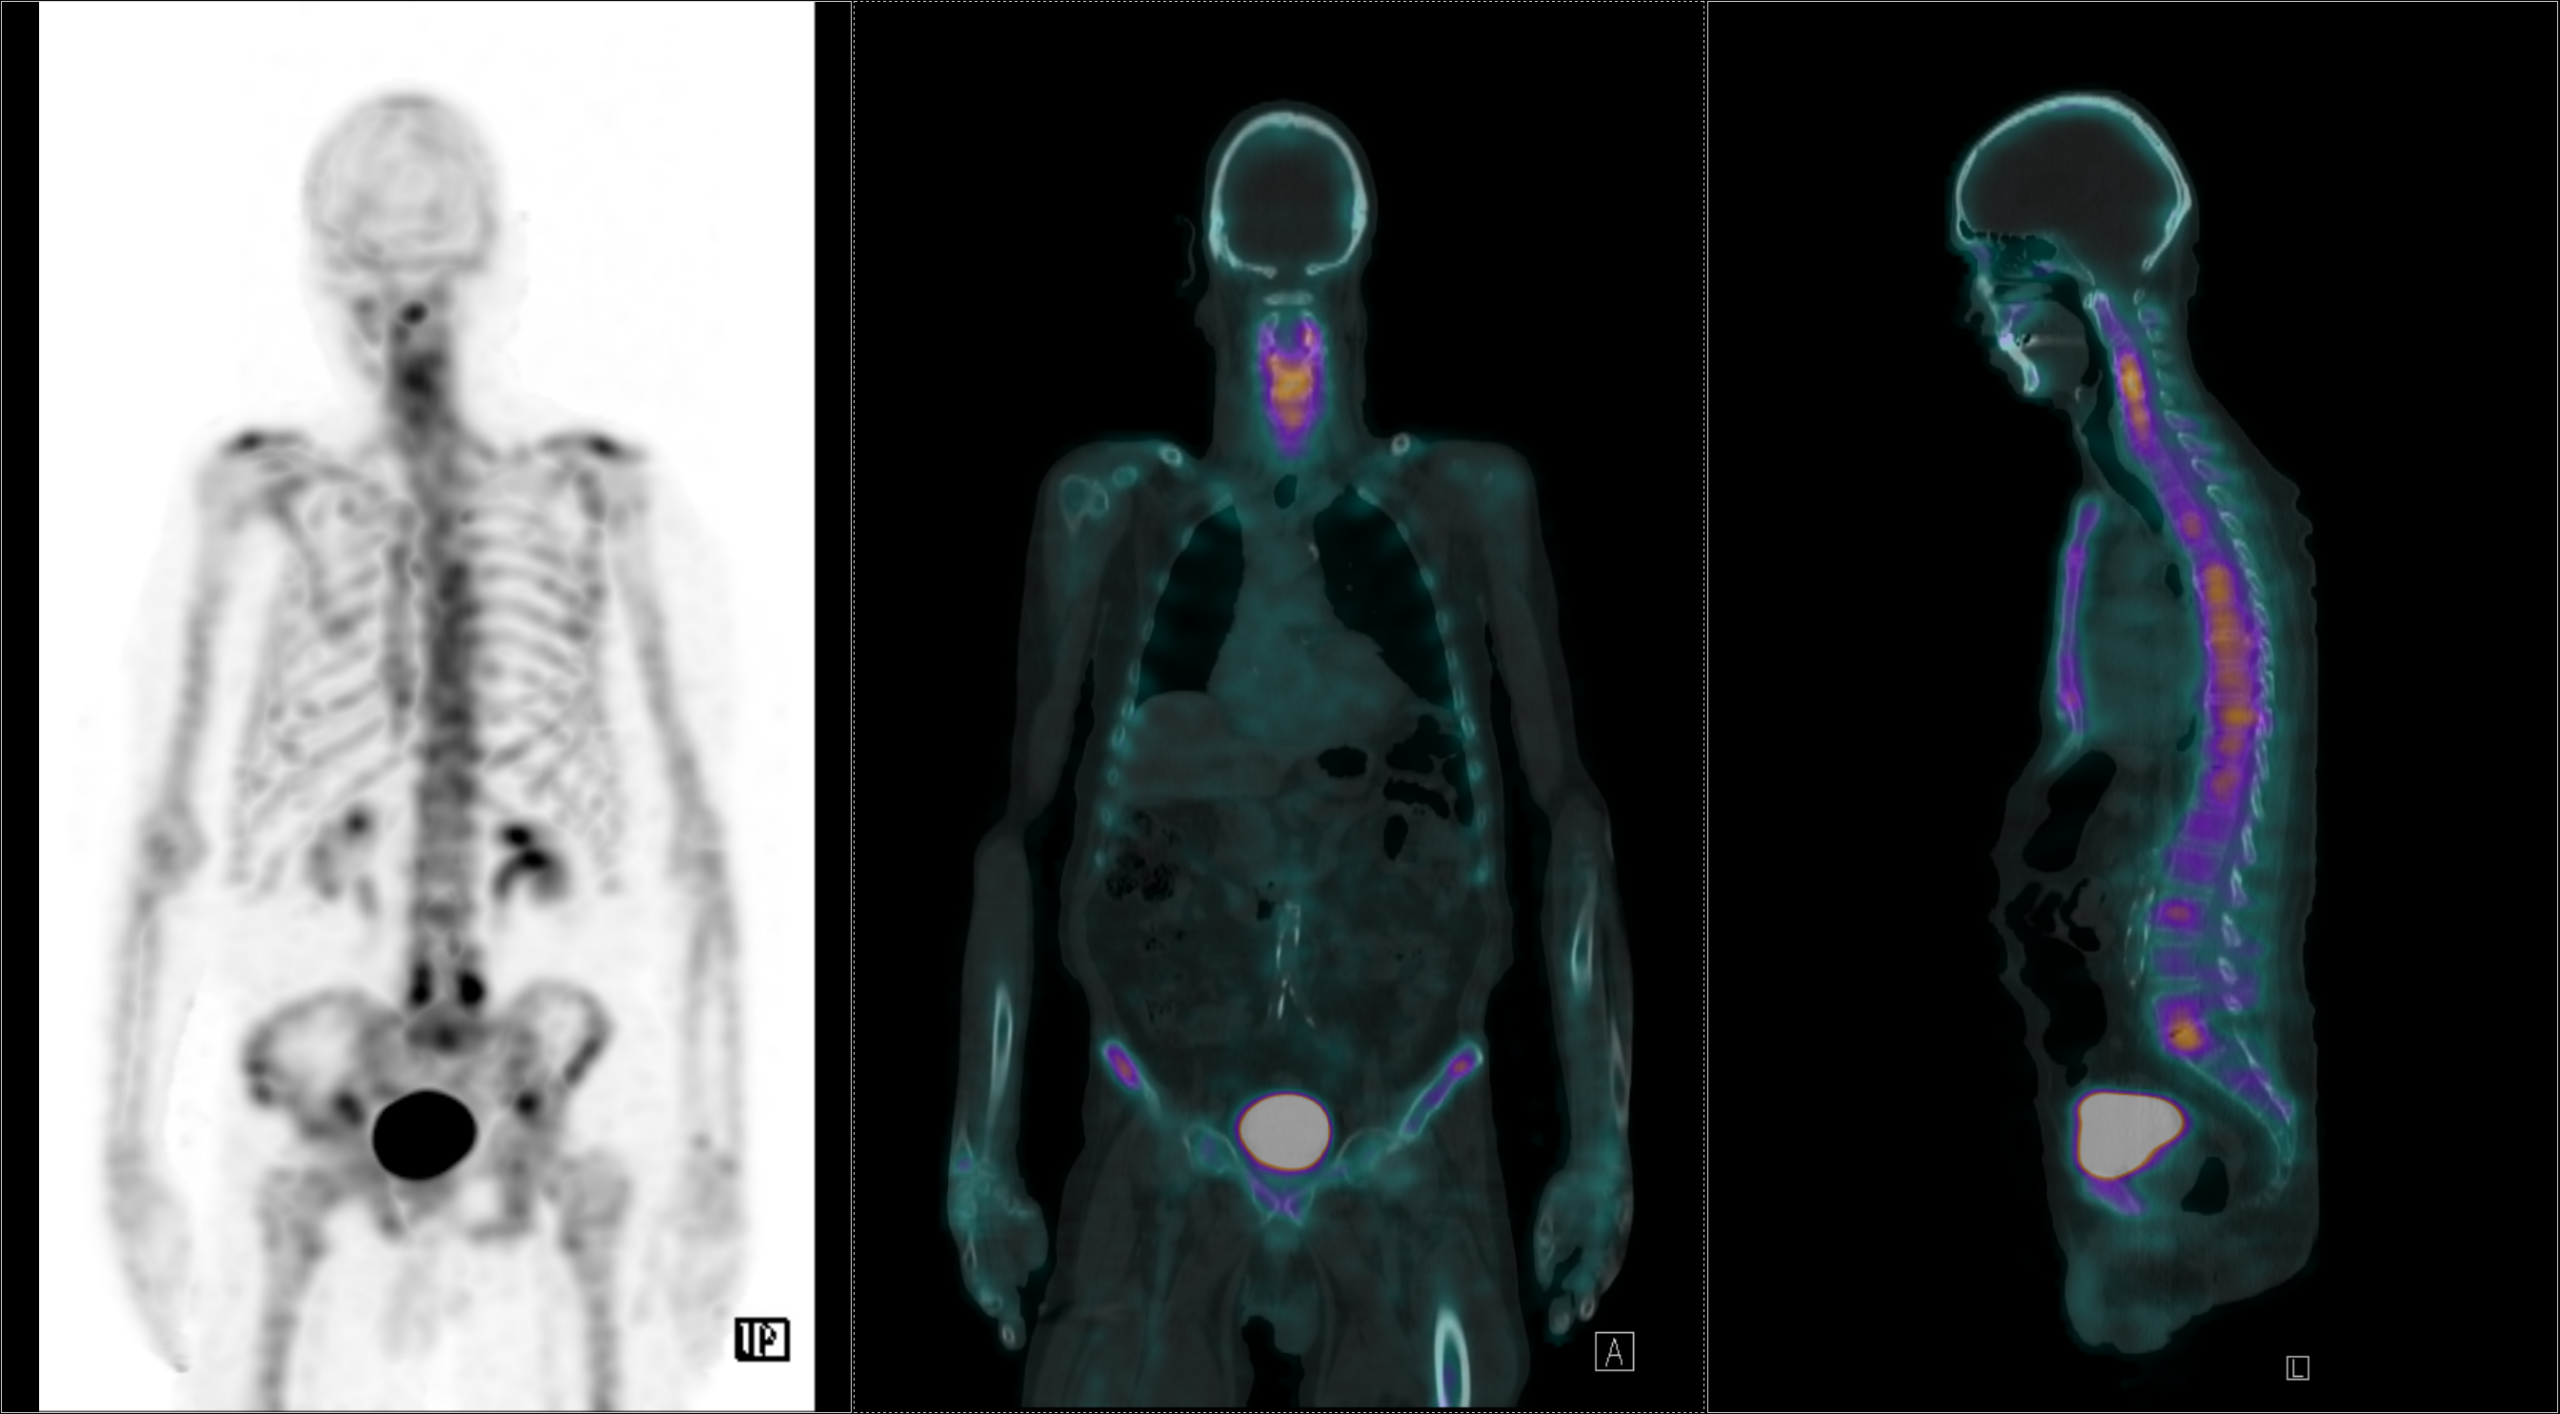

Η θεραπεία με Lu-177 DOTATATE (PRRT – Peptide Receptor Radionuclide Therapy) αποτελεί μια από τις πλέον εξελιγμένες μορφές στοχευμένης ραδιονουκλιδικής θεραπείας για νευροενδοκρινείς όγκους του γαστρεντερικού και του παγκρέατος, αξιοποιώντας την υπερέκφραση των υποδοχέων σωματοστατίνης στους νεοπλασματικούς ιστούς. Η διαδικασία περιλαμβάνει τον ακριβή προσδιορισμό της έκτασης της νόσου μέσω Ga68 DOTATATE PET/CT, την επιβεβαίωση υψηλής έκφρασης υποδοχέων SSTR και στη συνέχεια τη χορήγηση του Λουτέσιο-177 DOTATATE, το οποίο δεσμεύεται εκλεκτικά στους ανωτέρω υποδοχείς. Η ενέργεια του β-εκπομπού Λουτέσιου επιτρέπει στοχευμένη κυτταροτοξική δράση μέσα στον όγκο, με ελάχιστη διασπορά σε υγιείς ιστούς. Η σύγχρονη πρακτική ενσωματώνει ειδικά λογισμικά δοσιμετρίας, που υπολογίζουν την απορροφούμενη δόση σε κρίσιμα όργανα (ήπαρ, νεφροί, μυελός) και την πραγματική δόση στον όγκο, επιτρέποντας εξατομικευμένο σχεδιασμό και βελτιστοποιημένη θεραπευτική στρατηγική. Μετά από κάθε κύκλο θεραπείας πραγματοποιείται απεικονιστικός έλεγχος, αξιολόγηση τοξικοτήτων και συνολική εκτίμηση ανταπόκρισης, καθοδηγώντας τις επόμενες φάσεις της θεραπείας. Το Lu-177 DOTATATE έχει αποδειχθεί εξαιρετικά αποτελεσματικό στη σταθεροποίηση και συχνά στη συρρίκνωση της νόσου, παρατείνοντας την επιβίωση και βελτιώνοντας σημαντικά την ποιότητα ζωής των ασθενών.

Το Lu-177 PSMA αποτελεί μια στοχευμένη ραδιονουκλιδική θεραπεία για ασθενείς με ορμονοάντοχο μεταστατικό καρκίνο του προστάτη (mCRPC), αξιοποιώντας τη υπερέκφραση του PSMA (Prostate-Specific Membrane Antigen) στα καρκινικά κύτταρα. Προηγείται PSMA PET/CT για ακριβή χαρτογράφηση της νόσου και επιβεβαίωση επαρκούς πρόσληψης του ραδιοφάρμακου. Το Lu-177 PSMA συνδέεται στους PSMA-υποδοχείς, επιτρέποντας στοχευμένη ακτινική δράση υψηλής κυτταροτοξικότητας σε μεταστατικές εστίες οστών και μαλακών μορίων. Η χρήση εξειδικευμένων δοσιμετρικών εργαλείων επιτρέπει την ποσοτική αποτίμηση της δόσης σε κρίσιμα όργανα (π.χ. σιελογόνοι αδένες, νεφροί, μυελός) και στον όγκο, συμβάλλοντας σε εξατομικευμένη θεραπευτική προσέγγιση. Μετά από κάθε κύκλο πραγματοποιείται PSMA PET/CT ή FDG PET/CT (όπου ενδείκνυται), καθώς και στενός αιματολογικός έλεγχος για αξιολόγηση της ανταπόκρισης και των πιθανών τοξικοτήτων. Η θεραπεία έχει αποδειχθεί ιδιαίτερα αποτελεσματική στη μείωση του καρκινικού φορτίου, στη βελτίωση του πόνου, στη μείωση των επιπέδων PSA και στη σημαντική παράταση του προσδόκιμου επιβίωσης σε ασθενείς με εκτεταμένη και ανθεκτική νόσο.

Με τη SPECT‑CT ποσοτικοποίηση υπολογίζουμε απορροφούμενες δόσεις σε όγκους και όργανα‑στόχους (νεφροί, σιελογόνοι, ήπαρ, μυελός κ.ά.). Αυτό:

Με βάση τα σύγχρονα Guidelines όλων των διεθνών ογκολογικών εταιρειών η μεταθεραπευτική απεικόνιση είναι προαπαιτούμενο για την έναρξη-συνέχιση της θεραπείας και το βέλτιστο αποτέλεσμα αυτής.